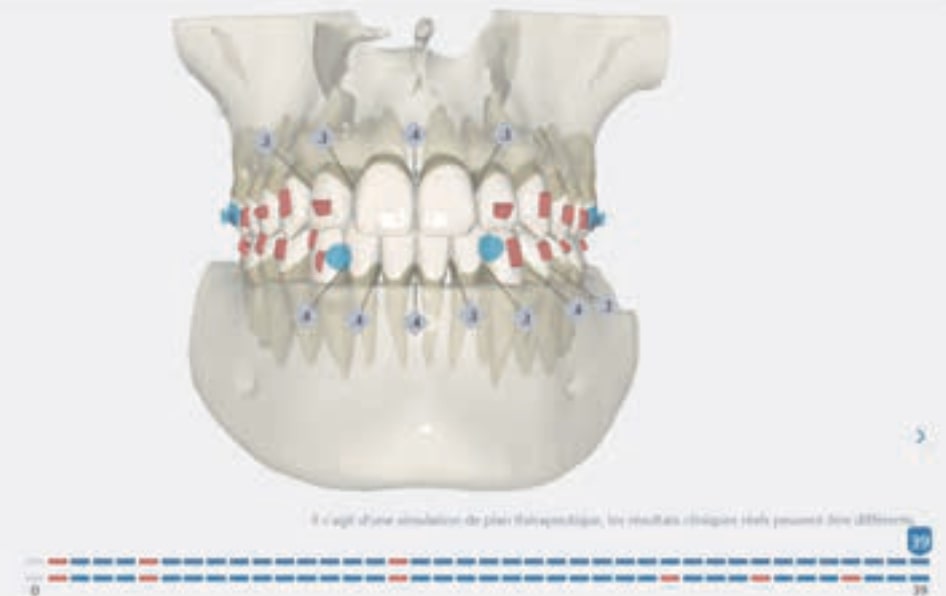

Number of aligners: 39

Protocoles and features A8 Molar distalization

• Distalization of the Third and Fourth Quadrants: Move the teeth distally in these quadrants to achieve a Class I relationship using the A8 protocol, improving the patient’s dental alignment and occlusion.